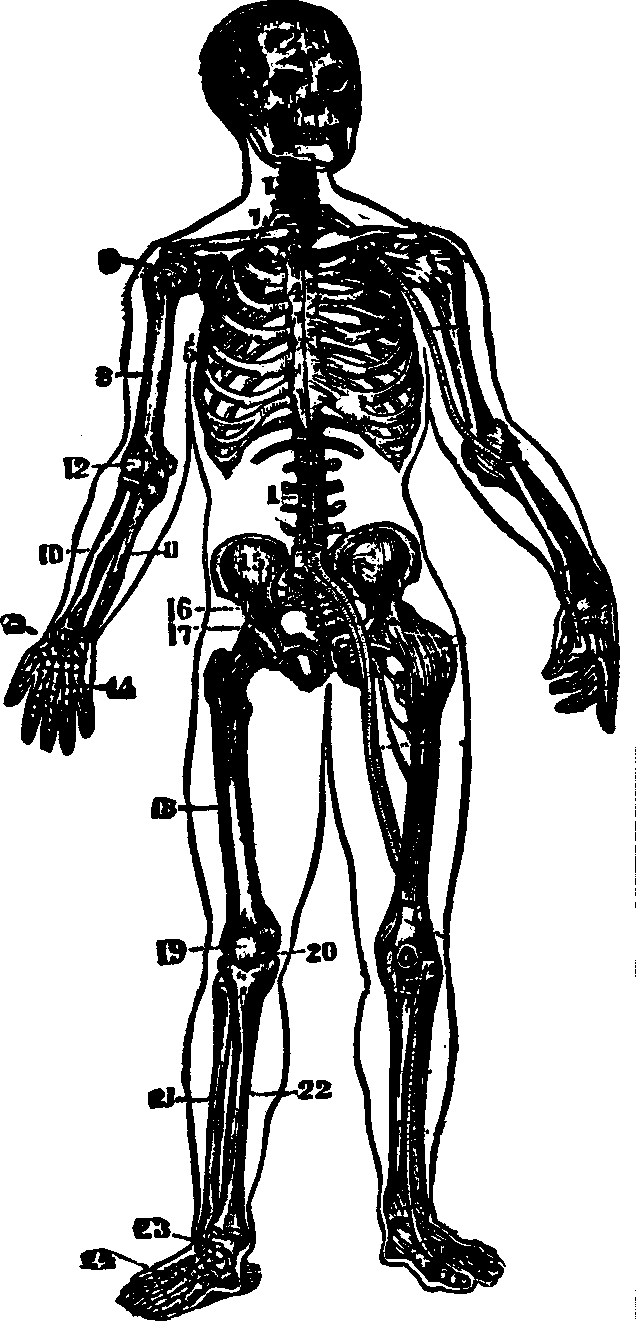

Fig. 16. 1. Portions of

the backbone. 2. Cranial bones. 4. Breast-bone. 5. Ribs.

7. Collar-bone. 8. Arm-bone (humerus). 9.

Shoulder-joint. 10, 11. Bones of the fore-arm (ulna and radius).

12. Elbow-joint. 13. Wrist-joint. 14. Bones of the

hand. 15, 16. Pelvic bones. 17. Hip-joint. 18. Femur.

19, 20. Bones of the knee-joint. 21, 22. Fibula and tibia.

23. Ankle bone. 24. Bones of the foot.

The Bones of the Upper Extremities are sixty-four in number, and are classified as follows: The Scapula, [pg 26]Clavicle, Humerus, Ulna, Radius, Carpus, Metacarpus, and Phalanges. The Scapula, or shoulder-blade, is an irregular, thin, triangular bone, situated at the posterior part of the shoulder, and attached to the upper and back part of the chest. The Clavicle, or collar-bone, is located at the upper part of the chest, between the sternum and scapula, and connects with both. Its form resembles that of the italic letter f, and it prevents the arms from sliding forward. The Humerus, the first bone of the arm, is long, cylindrical, and situated between the scapula and fore-arm. The Ulna is nearly parallel with the radius, and situated on the inner side of the fore-arm. It is the longer and larger of the two bones, and in its articulation with the humerus, forms a perfect hinge-joint. The Radius, so called from its resemblance to a spoke, is on the outer side of the fore-arm, and articulates with the bones of the wrist, forming a joint. The ulna and radius also articulate with each other at their extremities. The Carpus, or wrist, consists of eight bones, arranged in two rows. The Metacarpus, or palm of the hand, is composed of five bones [pg 27]situated between the carpus and fingers. The Phalanges, fourteen in number, are the bones of the fingers and thumb, the fingers each having three and the thumb two.

The Bones of the Lower Extremities, sixty in number, are classed as follows: The Femur, Patella, Tibia, Fibula, Tarsus, Metatarsus, and Phalanges. The Femur, or thigh-bone, is the longest bone in the body. It has a large round head, which is received into the acetabulum, thus affording a good illustration of a ball and socket joint. The Patella, or knee-pan, is the most complicated articulation of the body. It is of a round form, connects with the tibia by means of a strong ligament, and serves to protect the front of the joint, and to increase the leverage of the muscles attached to it, by causing them to act at a greater angle. The Tibia, or shin bone, is enlarged at each extremity and articulates with the femur above and the astragalus, the upper bone of the tarsus, below. The Fibula, the small bone of the leg, is situated on the outer side of the tibia, and is firmly bound to it at each extremity. The Tarsus, or instep, is composed of seven bones, and corresponds to the carpus of the upper extremities. The Metatarsus, the middle of the foot, bears a dose resemblance to the metacarpus, and consists of five bones situated between the tarsus and the phalanges. The tarsal and the metatarsal bones are so united as to give an arched appearance to the foot, thus imparting elasticity. The Phalanges, the toes, consist of fourteen bones, arranged in a manner similar to that of the fingers.